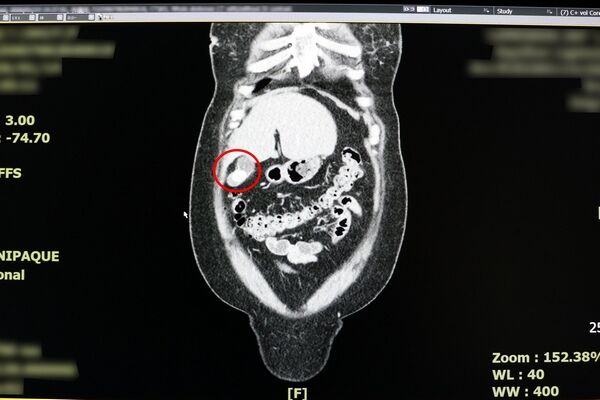

▲電腦斷層掃描顯示膽囊發炎位置。(圖/聯新國際提供)

反覆上腹部疼痛時,別再以為只是胃病,當心恐是膽囊炎作祟!一名38歲女性日前因持續2天劇烈上腹痛,先後到診所與地區醫院就診,皆被診斷為胃炎,服藥與打止痛針仍未改善,求診聯新國際醫院急診室,經朱海慶醫師詢問病史與電腦斷層檢查,會診一般外科張堯任醫師,確診為急性膽囊炎。